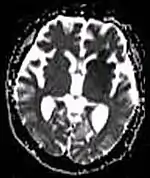

Diffusion weighted (DWI)ConventionalDWIMeasure of Brownian motion of water molecules.[66] High signal within minutes of cerebral infarction (pictured).[67]

Apparent diffusion coefficientADCReduced T2 weighting by taking multiple conventional DWI images with different DWI weighting, and the change corresponds to diffusion.[68] Low signal minutes after cerebral infarction (pictured).[69]